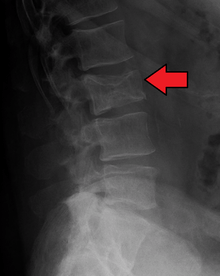

Bone pain

Bone pain affects almost 70% of patients and is the most common symptom.[11] Myeloma bone pain usually involves the spine and ribs, and worsens with activity. Persistent localized pain may indicate a pathological bone fracture. Involvement of the vertebrae may lead to spinal cord compression or kyphosis. Myeloma bone disease is due to the overexpression of receptor activator for nuclear factor κ B ligand (RANKL) by bone marrow stroma. RANKL activates osteoclasts, which resorb bone. The resultant bone lesions are lytic (cause breakdown) in nature and are best seen in plain radiographs, which may show "punched-out" resorptive lesions (including the "raindrop" appearance of the skull on radiography). The breakdown of bone also leads to release of calcium into the blood, leading to hypercalcemia and its associated symptoms.

Work-up

The work-up of suspected multiple myeloma includes a skeletal survey. This is a series of X-rays of the skull, axial skeleton and proximal long bones. Myeloma activity sometimes appear as "lytic lesions" (with local disappearance of normal bone due to resorption), and on the skull X-ray as "punched-out lesions" (pepper pot skull). Magnetic resonance imaging (MRI) is more sensitive than simple X-ray in the detection of lytic lesions, and may supersede skeletal survey, especially when vertebral disease is suspected. Occasionally a CT scan is performed to measure the size of soft tissue plasmacytomas. Bone scans are typically not of any additional value in the workup of myeloma patients (no new bone formation; lytic lesions not well visualized on bone scan).